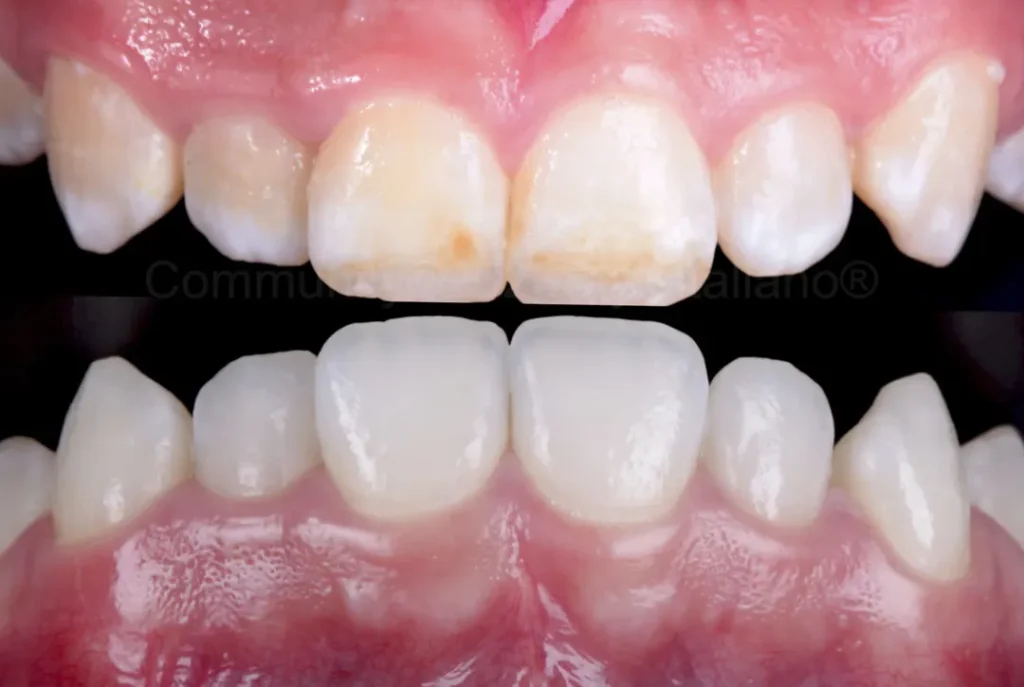

White Spots Treatment in Beirut

Restore a uniform, natural tooth color without damaging your enamel.

White spot treatment (ICON infiltration) is a modern, minimally invasive solution to eliminate white stains caused by braces or enamel defects. This painless procedure blends the color of your teeth without drilling, helping you achieve a more aesthetic and balanced smile in just one session.

Composite Bonding in Beirut

A simple, fast, and natural solution to improve your smile in one visit.

Composite bonding is a minimally invasive cosmetic treatment used to repair chipped teeth, close gaps, and improve shape and color. Using high-quality materials and precise techniques, we can restore your teeth in a single session with results that blend seamlessly with your natural smile.